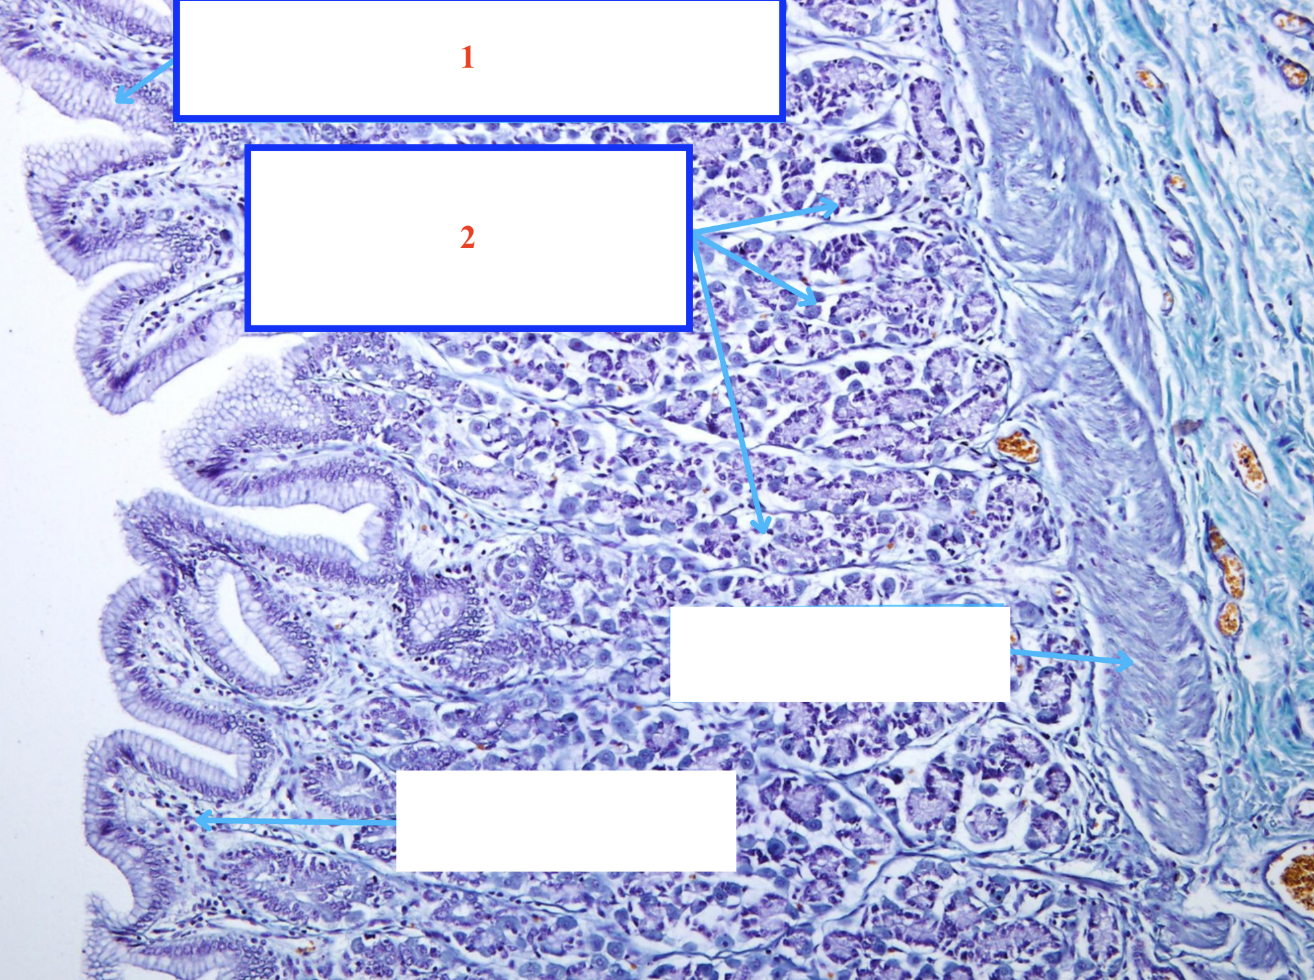

Cấu trúc gì ? - Tiêu bản gì ?

Nhung mao tá tràng

Tuyến Lieberkühn tá tràng

Tuyến Brünner